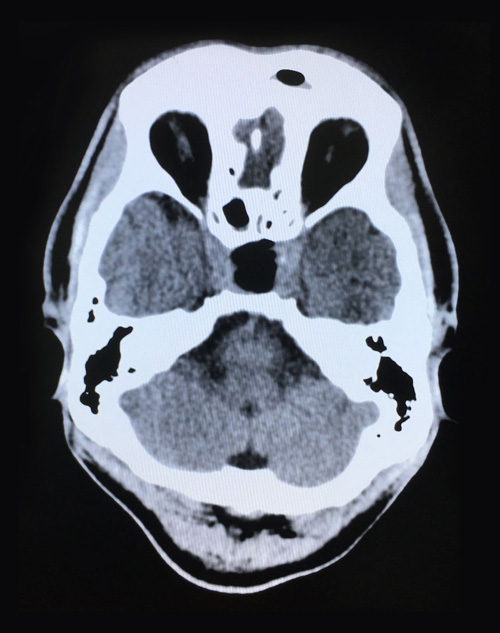

術(shù)后第二天影像:腫瘤切除干凈,鞍內(nèi)腦脊液填充